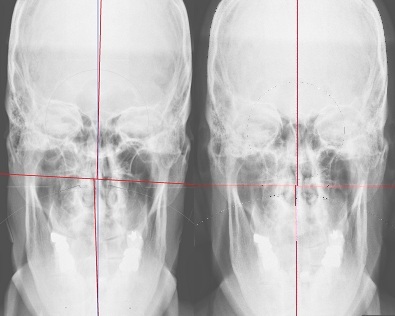

Before                                                       After

Which x-ray image do you think represents a more complete mind-body connection?  Feeling an internal disconnection?  Get your head on straight!